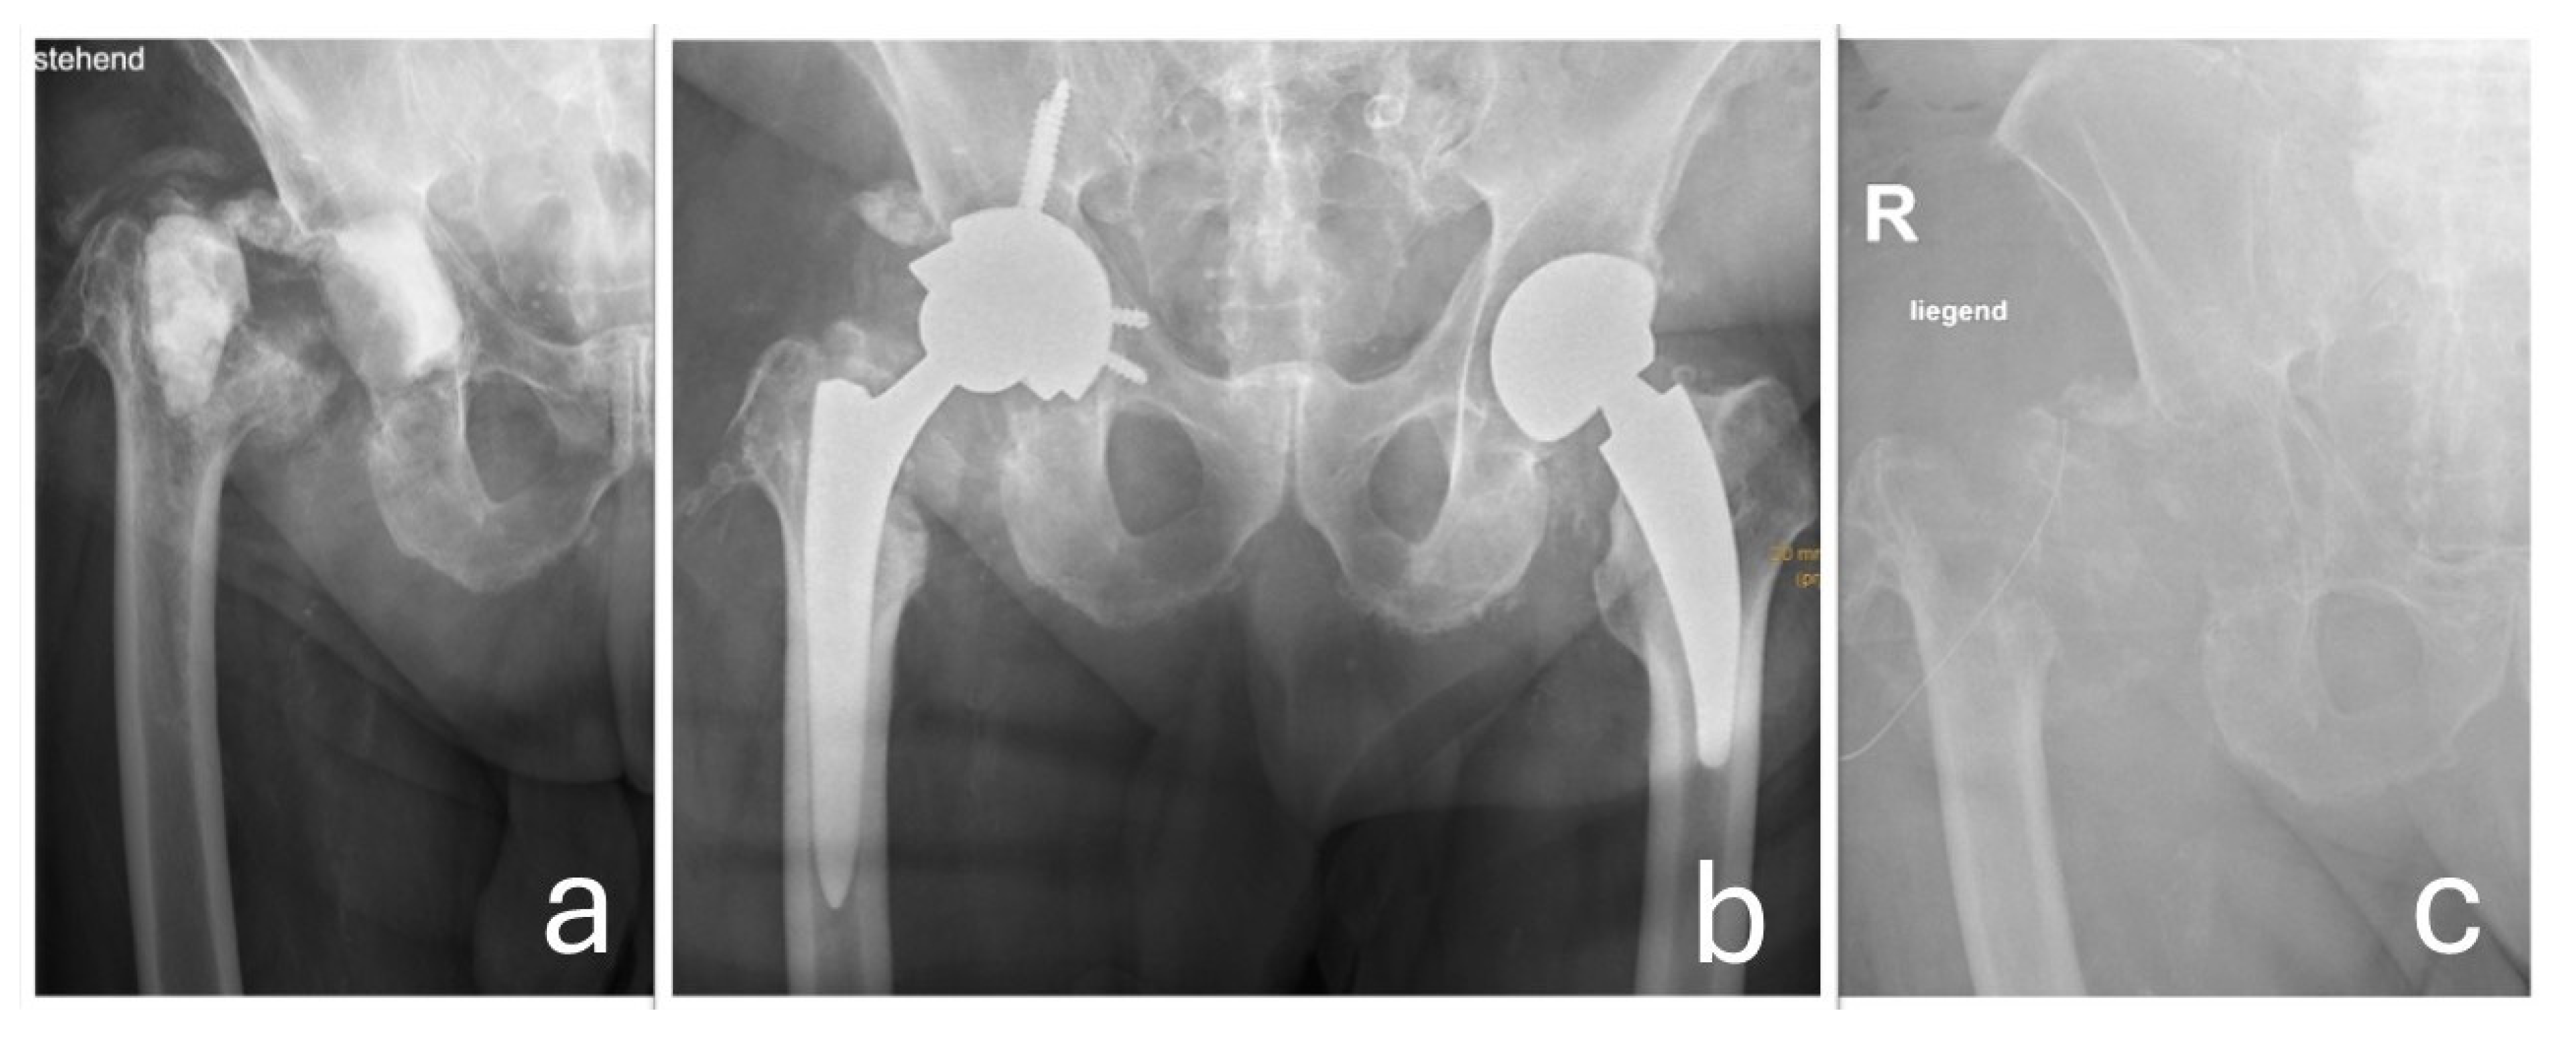

In 2017, a revision surgery was performed in the same hospital due to persistent hip joint pain and radiologically evident eccentric wear of the liner in the primary load-bearing zone. The liner was replaced with highly cross-linked polyethylene and a new metal head (Figure 3).

Figure 3. (a) The eccentric position of the prosthetic head is visible, indicating wear-related reaction of the sandwich-type inlay (metal shell encased in a polyethylene liner) in the main load-bearing zone. Additionally, heterotopic ossifications around the hip joint are observed. (b) The condition after the head/inlay exchange. The new metal head is now centrally positioned in the cross-linked polyethylene insert.